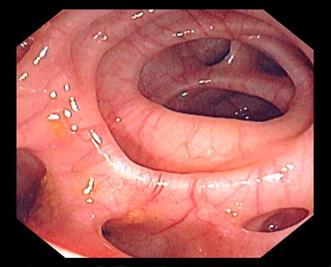

Es una infección del endocardio de las válvulas (superficie anterior).

Válvula nativa:

Endocarditis aguda causa más frecuente estafilococo aureus (estafilococo dorado) suele afectar a las válvulas sanas por lo general, fatal en 6 semanas si no se trata

Endocarditis subaguda causa más frecuente estreptococos del grupo viridans válvulas nativas dañadas previamente causa común de después de procedimientos dentales

En casos de estreptococo bovis se asocia con cáncer o pólipo en el colon.

Enterococos (especialmente, Enterococcus faecalis) causa común después de ITU nosocomiales

El flujo turbulento daña el endotelio de las válvulas activando la hemostasia y se forman vegetaciones asépticas formadas por plaquetas y fibrina (trombo estéril). Luego, estas se contaminan debido a una bacteriemia por un foco séptico, formándose una verruga bacteriana (vegetación séptica), la cual puede destruir la válvula (rotura de cuerdas tendinosas, músculo papilar) y formar abscesos, produciendo la clínica cardiaca; los émbolos sépticos que pasan a la circulación sistémica dan lugar a la clínica extracardiaca (en casos de ADVP, predominan los émbolos pulmonares).

La triada clínica es fiebre (95 %), soplo de regurgitación (85 %) y esplenomegalia (30 %) . Además, podría haber clínica extracardiaca producto de los émbolos sépticos al territorio de la arteria cerebral media, como hemiparesia por un ictus isquémico en pacientes jóvenes o manifestaciones embólicas pulmonares (tos, disnea y hemoptisis), que son más frecuentes en los pacientes ADVP.